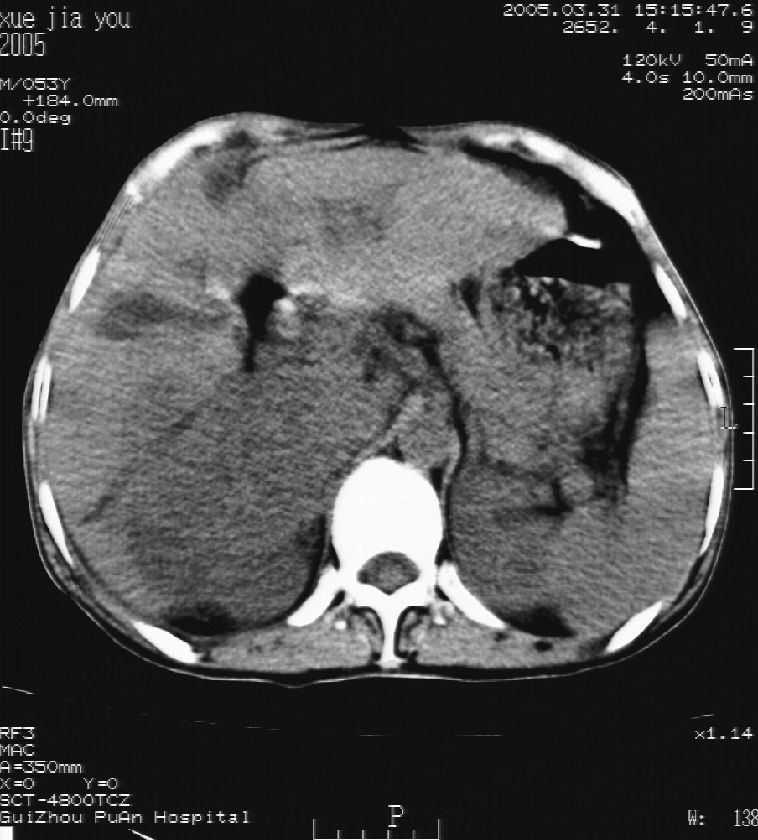

男 55岁  反复上腹痛1年,伴恶心呕吐。2005年做第一次检查后,到外院做b超检查提示肝囊肿,未做任何手术。2006年做过胆总管结石术。骨窗未见异常

这个病灶很有意思,怎么可能没有了呢?我考虑当时很可能是肝脏脓肿(b超示囊肿是有可能误诊的,因为影像表现都是低回声吗?),现在脓肿吸收了,肝脏萎缩,肝裂增宽了.别的肝叶代偿增大,不过现在左内叶的确有个占位,肝内多发结石,脾脏比以前大,不排除有肝硬化可能.建议增强扫描给于定性!!!!

肝硬化\\脾大,肝左叶肝癌可能性大,建议增强扫描.肝内胆管多发性结石.

1, 肝硬化,脾大;2,肝左叶肝癌可能性大,建议增强扫描.3,肝内胆管多发性结石.

考虑肝内胆管多发结石引起的肝内局部炎症,这样可以解释2005年肝右叶病灶的吸收和左叶新病灶.

肝硬化、脾大、肝内胆管多发结石。肝左叶低密度占位。建议增强扫描.排除肝癌